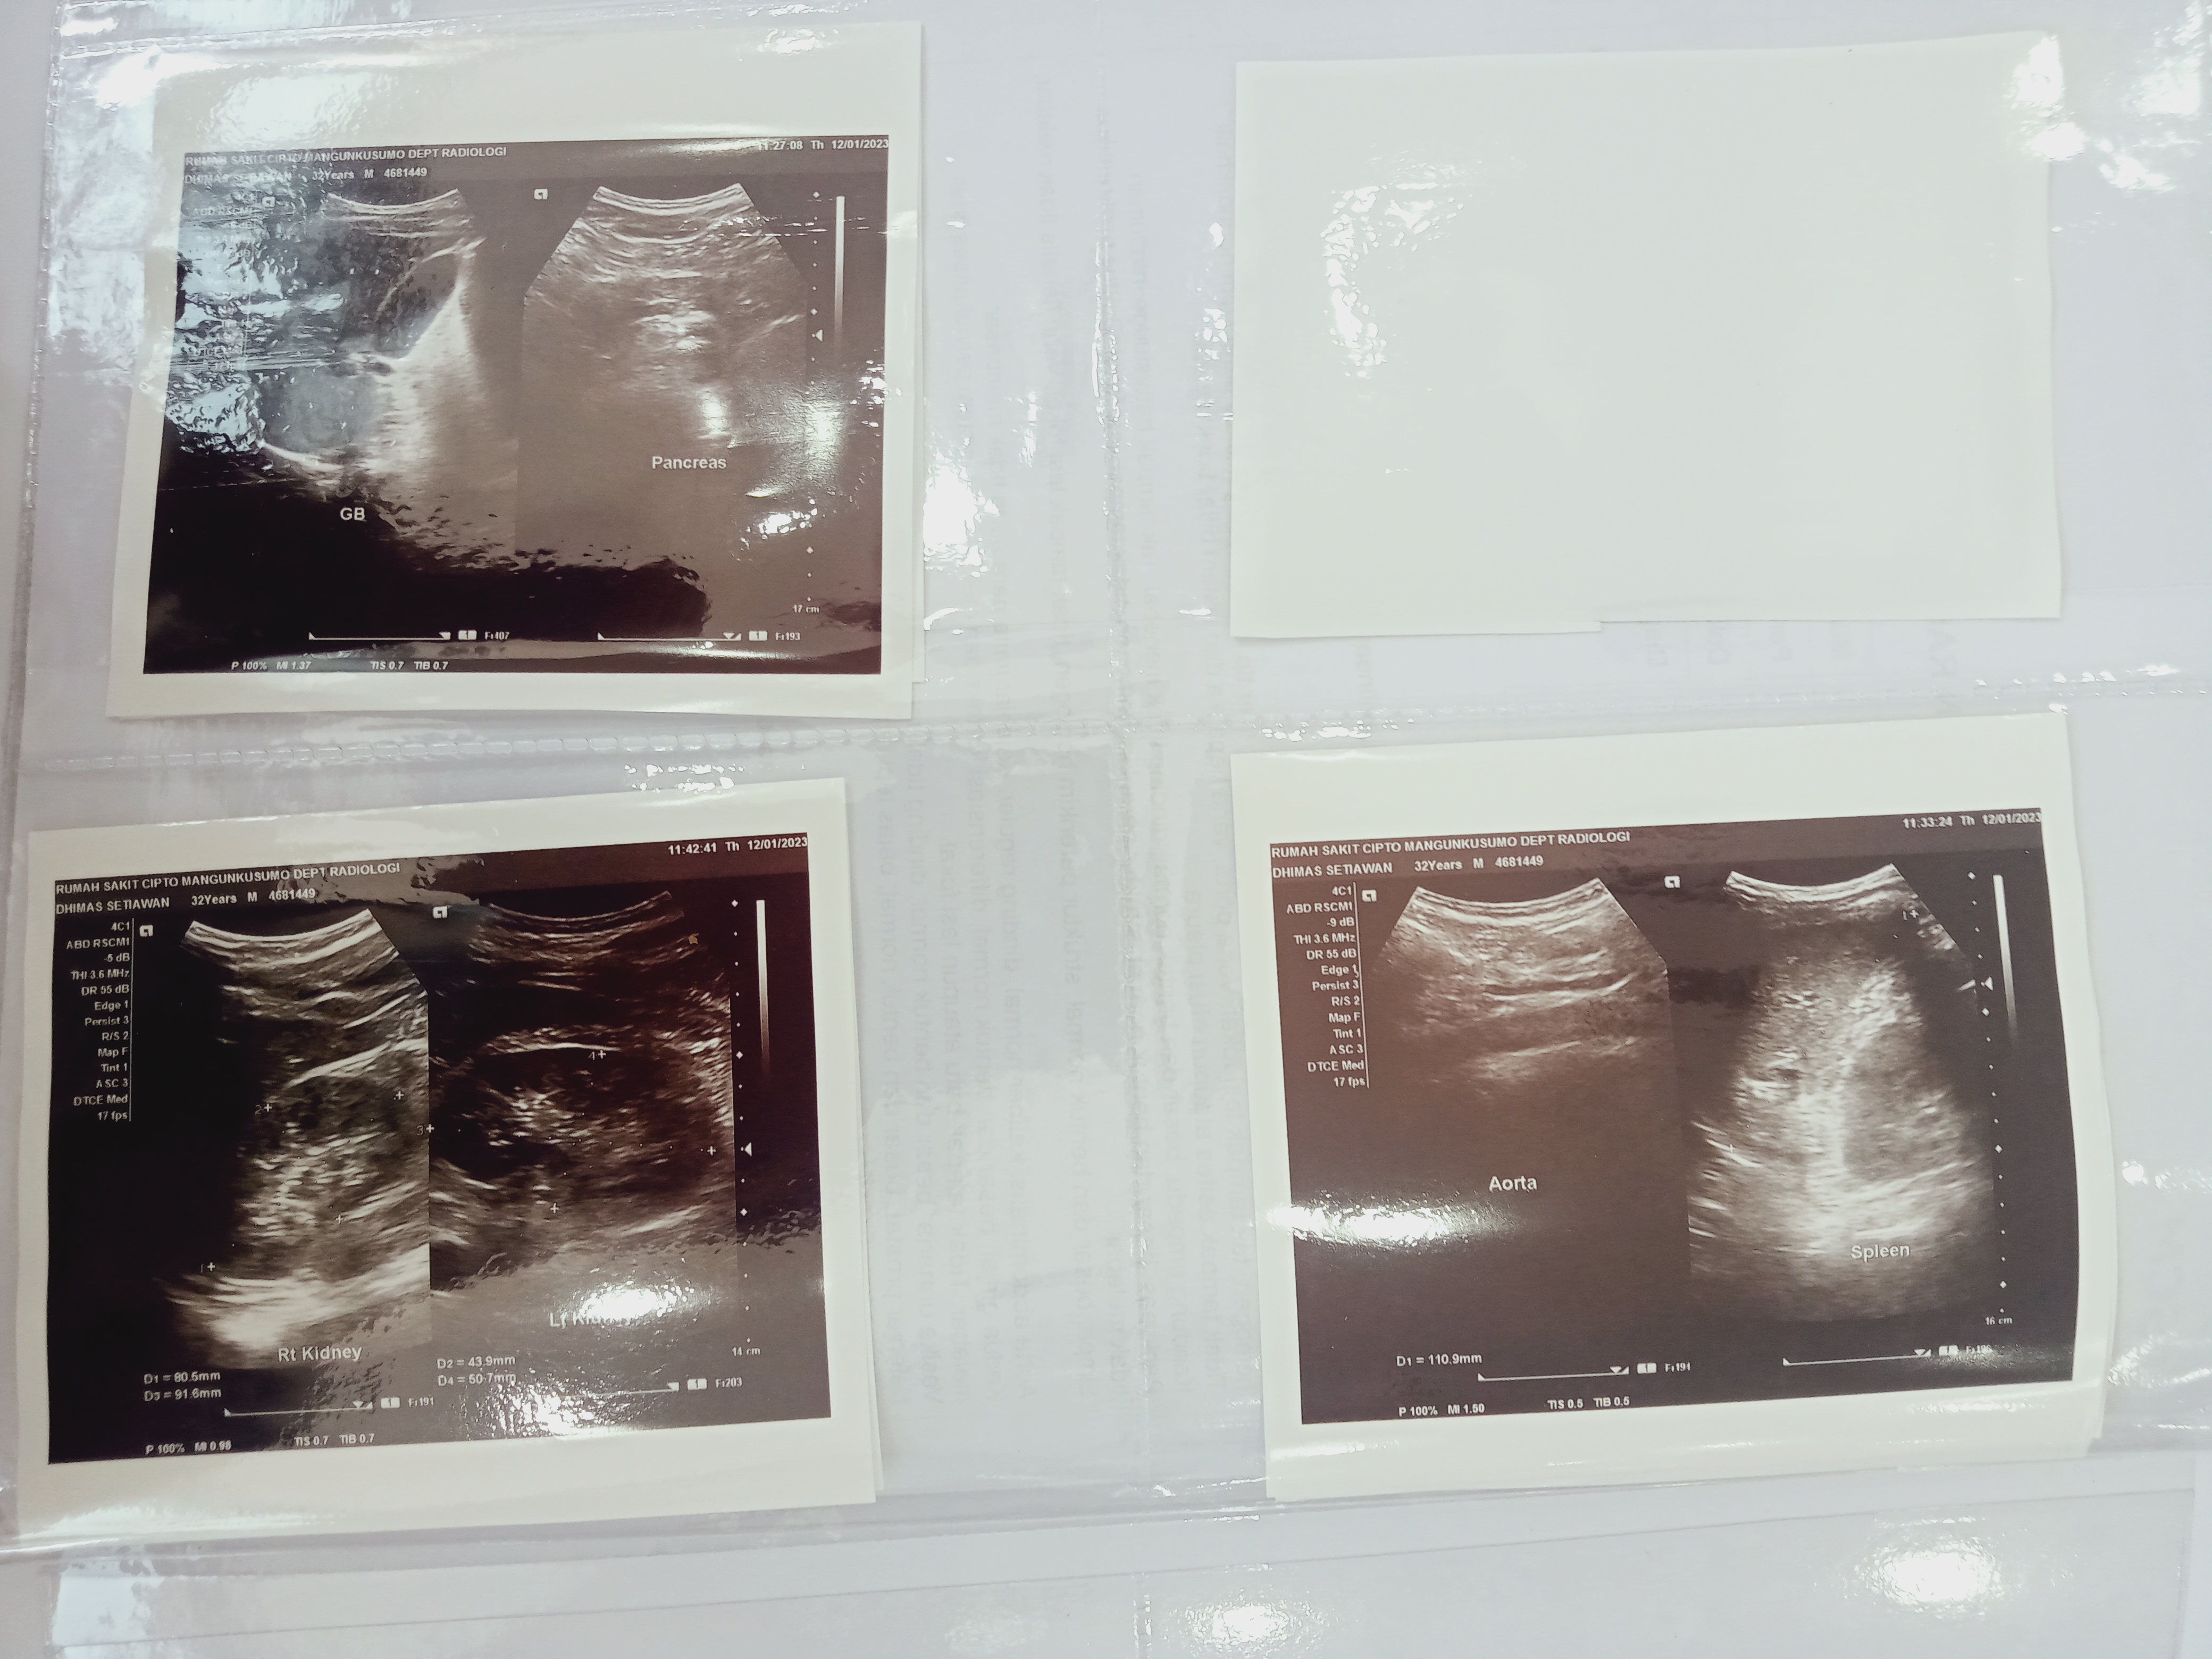

Hingga saat ini, Dhimas sudah genap satu bulan menjalani rangkaian pengobatan oleh tim dokter RSCM, cek lab, rontgen/USG dan pengambilan sampel (biopsi). Tindakan selanjutnya, akan dilakukan operasi dengan pembiusan total yang mana nantinya akan diangkat beberapa titik tumornya.